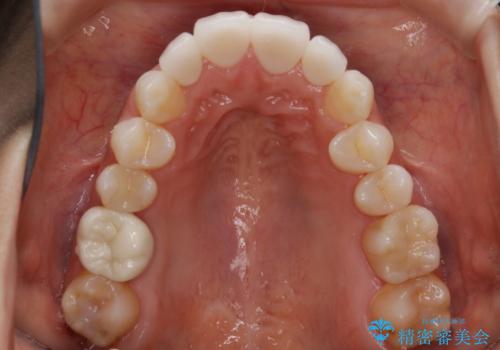

前歯・奥歯ともにセラミッククラウンで治療されている歯があったため、その歯にあまり影響が出ない範囲内で全体の噛み合わせが良くなるような動きを組み込んで治療を進めることとなりました。

被せ物がある場合

矯正治療前にセラミック等の被せ物をされている場合、それ自体の外形は矯正治療では変更することができないため、その他の天然歯の移動に影響を与えてしまう場合があります。また、治療上設定されるアタッチメント(歯の表面に付けるプラスチックの突起)が付かない場合が多く、歯のコントロールが不足する場合があります。